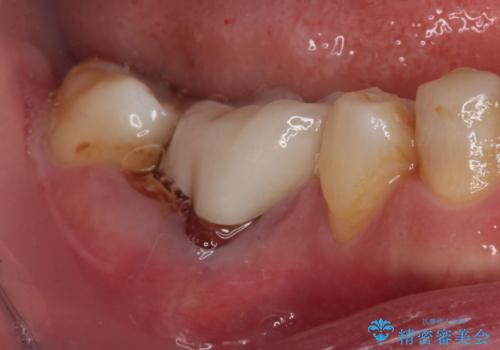

- 以前根管治療を行った歯が痛むとのことで来院された患者様です。

レントゲン写真より、歯根周辺に大きな病変(炎症により骨が溶けている状態)が認められたため、歯根が破折している可能性が示唆されました。

歯根が破折した歯は抜歯となるため、抜歯して病変の部分に骨が回復するのを待って、インプラントによる補綴治療を行うこととしました。